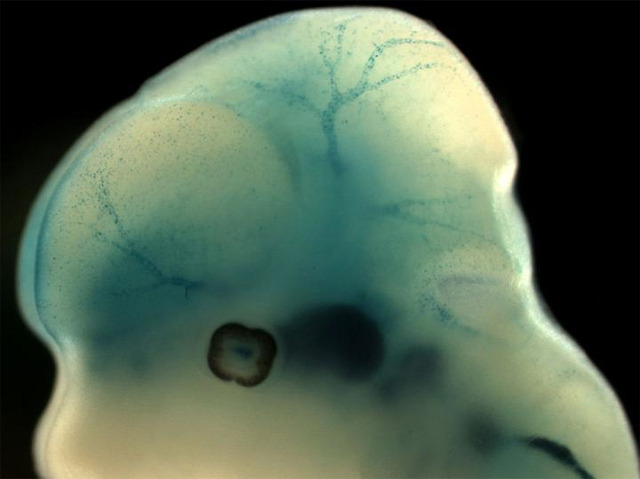

Barricading Against Strokes

As the control centre of our behaviours and most bodily functions, the brain is an especially precious organ. Consequently, it has its own unique protective shield: the blood-brain barrier – a tightly packed wall of endothelial cells lining the brain’s capillaries. Minimising transport of substances from the blood, the barrier thereby largely prevents pathogens, toxic proteins or other harmful agents from causing potentially fatal brain damage. Development of the barrier begins in the early embryo and is dependent on pericytes (the cells labeled blue in this embryonic mouse brain), which surround the growing vessels. Pericytes are present in all tissues, but scientists have learnt that brain pericytes express a special protein – Foxf2 – that drives barrier formation. Mice lacking this protein developed abnormal, leaky barriers and suffered bleeding on the brain – a cause of stroke. The findings suggest that aberrant expression of Foxf2 in pericytes might increase a person’s stroke susceptibility.